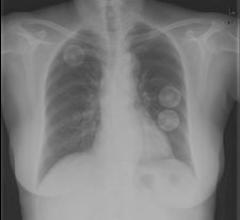

May 7, 2008 - GE Healthcare signed a nonexclusive agreement with Merck & Co. to share technology on imaging of the lungs ...